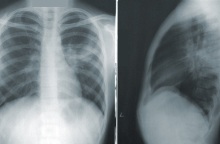

Η νέα πνευμονία «χτυπάει» κυρίως παιδιά

Την εκτίμηση ότι δεν χρήζει λόγος ανησυχίας για τη «μυστηριώδη» πνευμονία στην Κίνα εξέφρασε ο Δημήτρης Παρασκευής, σημειώνοντας ότι δεν θα έχουμε νέα πανδημία, καθώς εμφανίζεται κυρίως σε παιδιά.

Ο καθηγητής, επικαλούμενος πάντα στοιχεία που έχουν αναφέρει οι αρχές της Κίνας στον ΠΟΥ, επισημαίνει ότι πρόκειται για λοιμώξεις του αναπνευστικού, που εντοπίζονται κυρίως σε παιδιά και αφορούν γνωστά παθογόνα, τα οποία κυκλοφορούν αυτή την περίοδο, όπως ο ιός της γρίπης, ο RSV, ή ο Sars- Cov2.